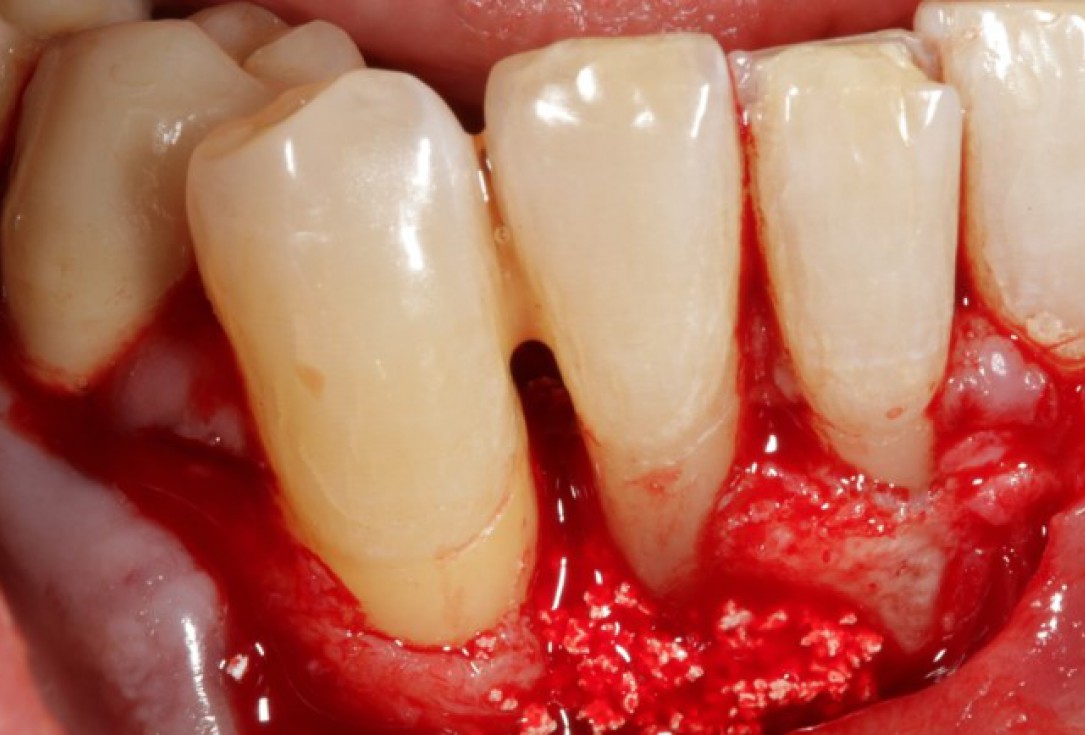

06/08 - Application of a particulate synthetic bone grafting material.

Non-contained intrabony defect treated using Straumann® Emdogain® and a synthetic bone grafting material - Prof. Dr. Dr. A. Kasaj